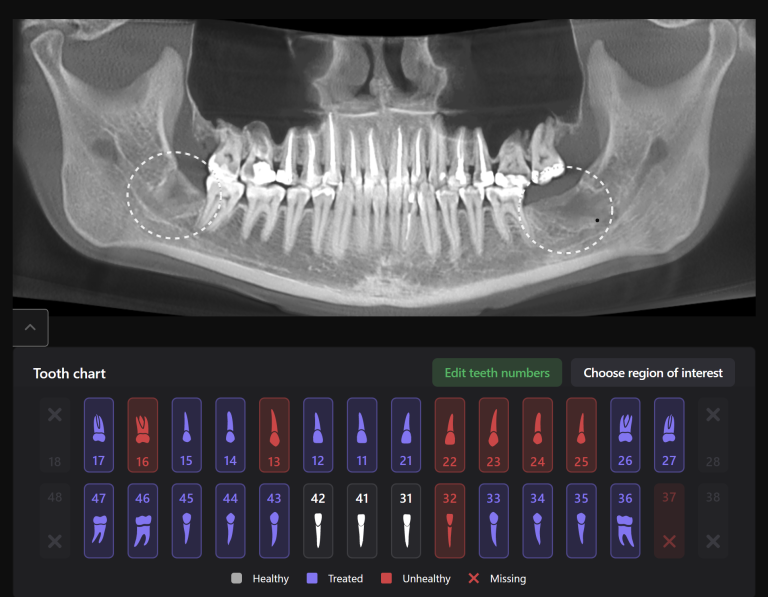

Planning implant placement using Diagnocat modules can help save the clinitian’s time and enhance the quality of implantological treatment

The result of collaboration with Diagnocat AI is a favorable outcome of the orthodontic and surgical stages of treatment